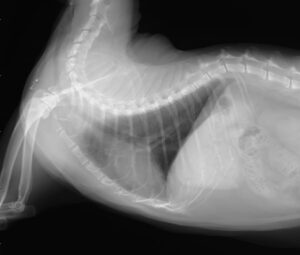

血液検査、胸部レントゲンや超音波検査を行い、ほかに咳を引き起こすような心臓病や肺の腫瘍などの病気がないか除外し、総合的に判断します。

ステロイド治療により改善した症例(右は治療後1カ月)